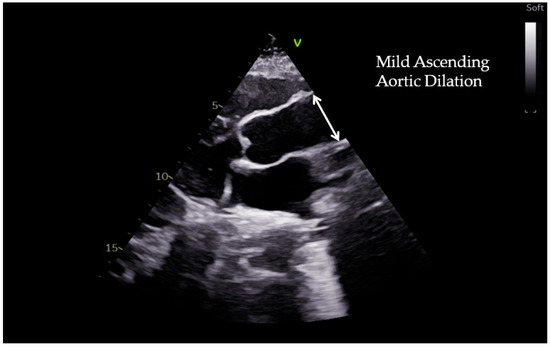

2. Measuring the Aortic Root and Ascending Aorta

3. Aortic Dilation in Athletes